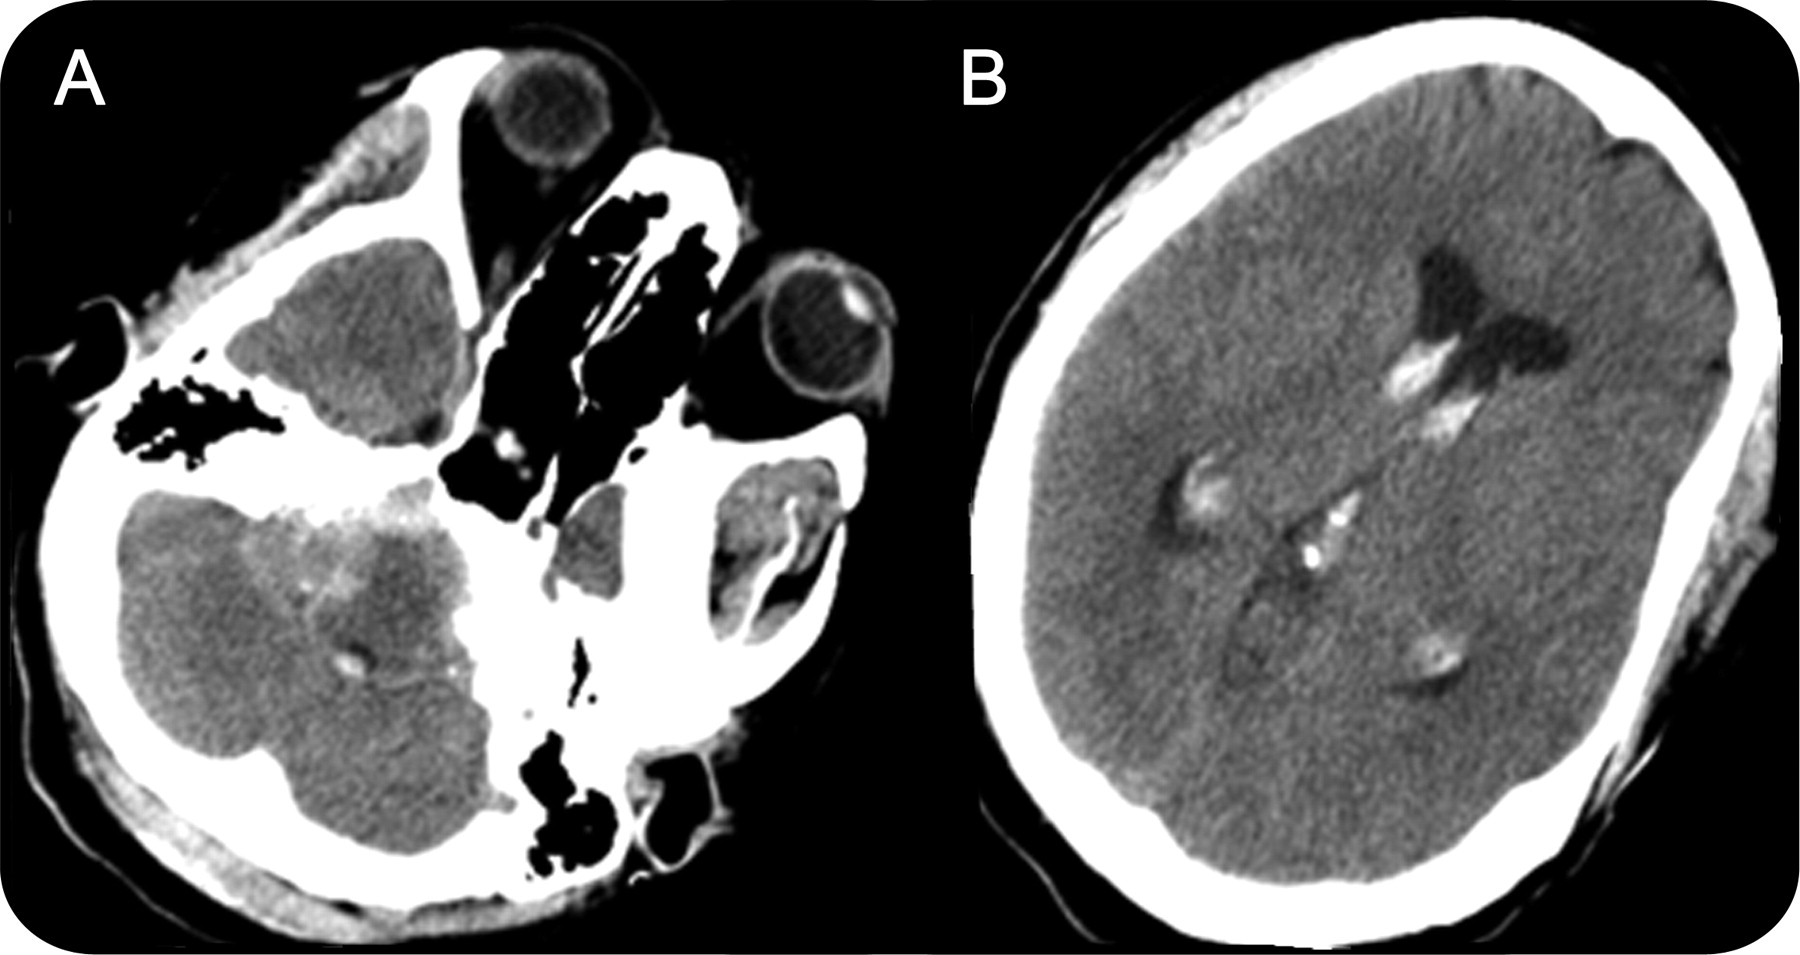

一个48岁的女人面对严重头痛辐射脖子和胸部,其次是短暂的意识丧失在急诊室。她苏醒后,病人描述了2年历史的右侧搏动性耳鸣和听力损失。她也有高血压和不遵守她的药物控制不好。在检查她的血压239/90毫米汞柱,不起眼的神经检查结果。脑蛛网膜下腔出血CT显示(图1A和B)。